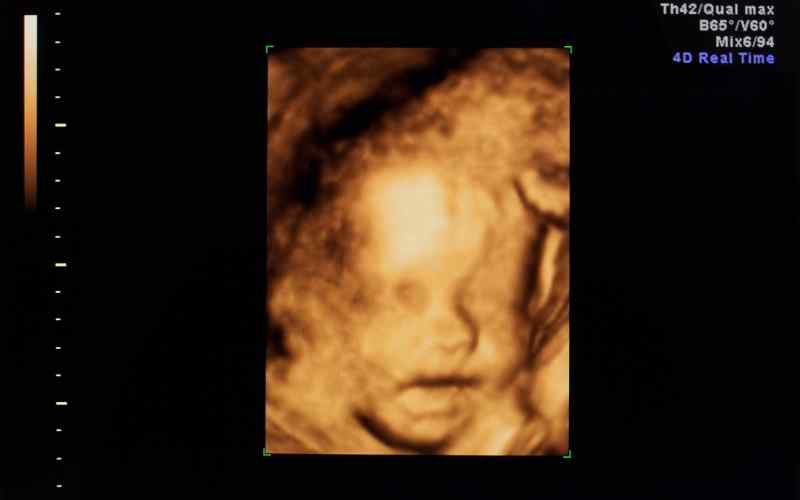

Vào tuần thứ 36 của thai kỳ, đầu thai nhi bắt đầu di chuyển đến vùng xương chậu và ở trong đó khoảng 2 tuần cuối. Trong khi đó, các cơ quan, bộ phận trên cơ thể của bé vẫn tiếp tục phát triển, đặc biệt là não bộ phát triển cực kỳ nhanh chóng.

Ở giai đoạn này, thai nhi có thể nhìn, nghe và có những cử chỉ như mút ngón tay, đạp,...Vì vậy, mẹ có thể trò chuyện giao tiếp với thai nhi để gắn kết tình cảm, giúp cho bé cảm nhận tốt hơn.